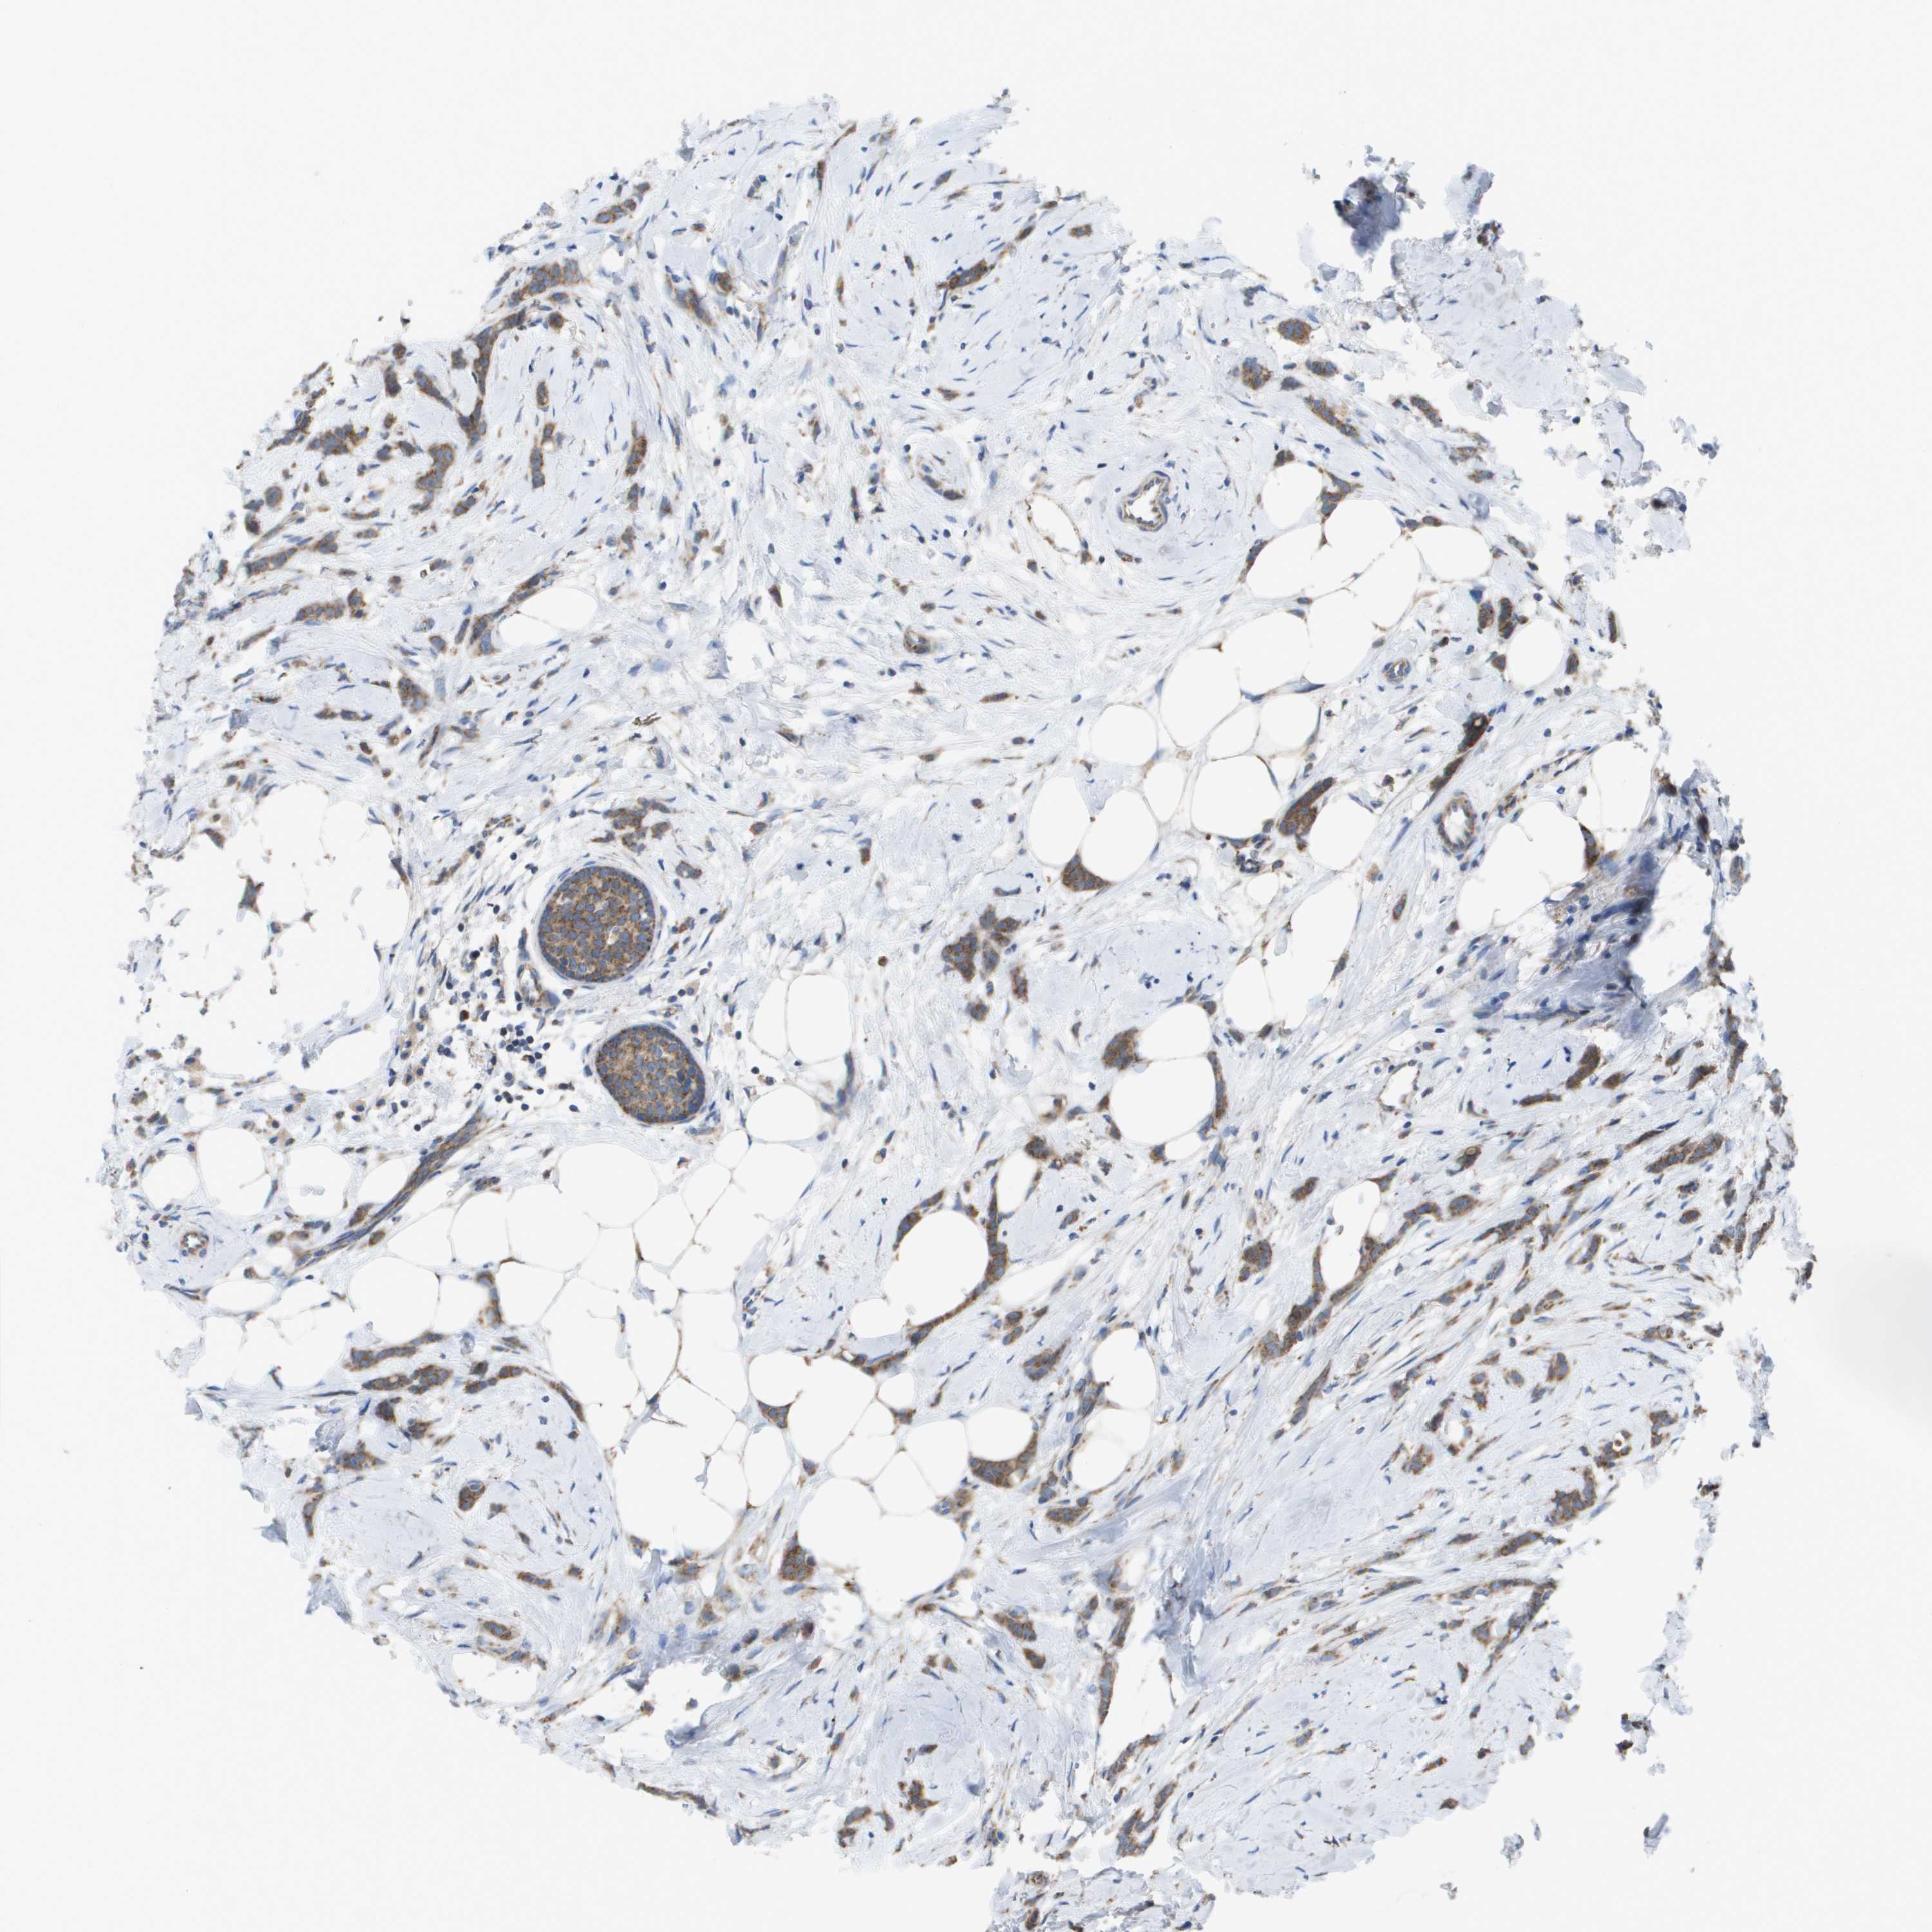

BRCA TCGA BRCA VALIDATION PROTEIN EXPRESSION

ANTIBODIES

AND

VALIDATION